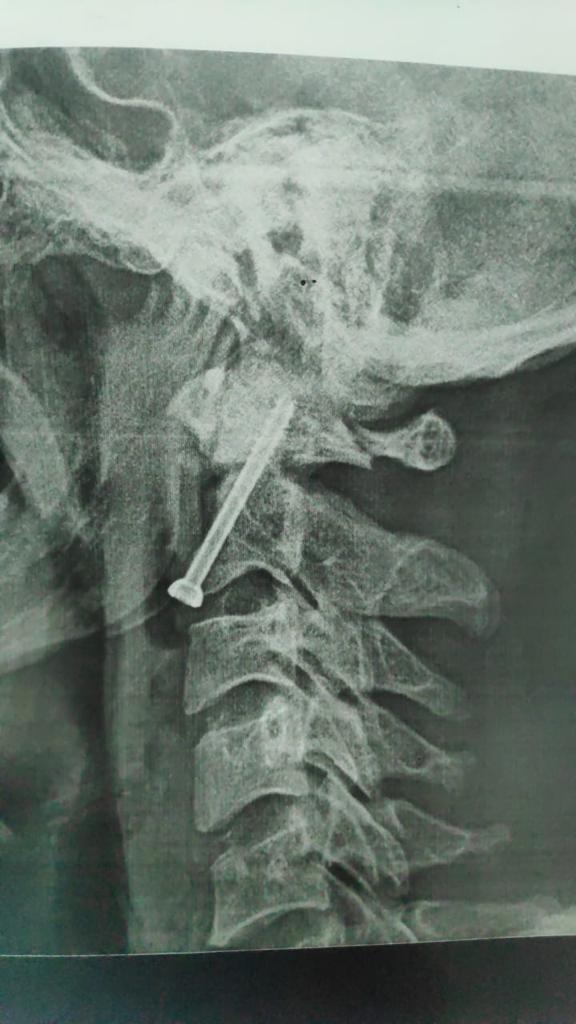

أكد الدكتور مصطفى عبد الخالق القائم بأعمال رئيس جامعة سوهاج أن فريق طبي متخصص من قسم جراحة العظام بالمستشفى الجامعي نجح في إجراء عملية جراحية لتثبيت كسر بالفقرة العنقية الثانية لشاب في العقد الثلاثين من عمره، وذلك بواسطة التدخل الجراحي من الأمام.

وقال "عبد الخالق" أن تلك الجراحة تعد من أكثر جراحات العمود الفقري خطورة نظرا لقربها من قاع المخ والحبل الشوكي وتحتاج إلى دقة ومهارة عالية في إجراؤها.

وأوضح الدكتور حمدي سعد مدير المستشفى الجامعي أنه بعد إجراء الفحوصات والإشاعات اللازمة للمريض تبين وجود كسر في الفقرة الثانية من العمود الفقري الرقبي، ويحتاج إلى جراحة عاجلة لتثبيت الفقرة العنقية، حيث كان هذا الكسر يشكل خطرًا كبيرًا على النخاع الشوكي وحياة المريض.

وذكر الدكتور عبدالرحمن الشيخ رئيس قسم جراحة العظام أنه بعد دراسة الحالة في ضوء نتائج الفحوصات الطبية، تم اتخاذ كافة التدابير التحضيرية للعملية، لافتًا الي ان الفريق الطبي الذي إجري العملية الجراحية للمريض كان تحت إشراف الدكتور أحمد صالح أستاذ جراحة العظام والعمود الفقري، حيث تم تثبيت الكسر بنجاح، وبدأ المريض الحركة بحرية تامة بمفرده بدون اي وسائل مساعدة.